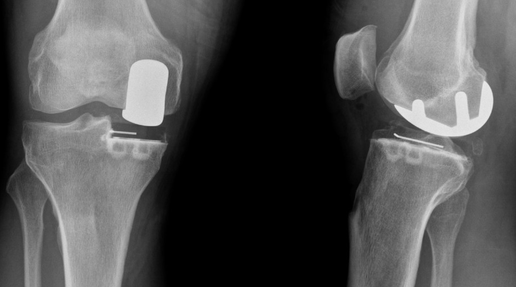

Genou